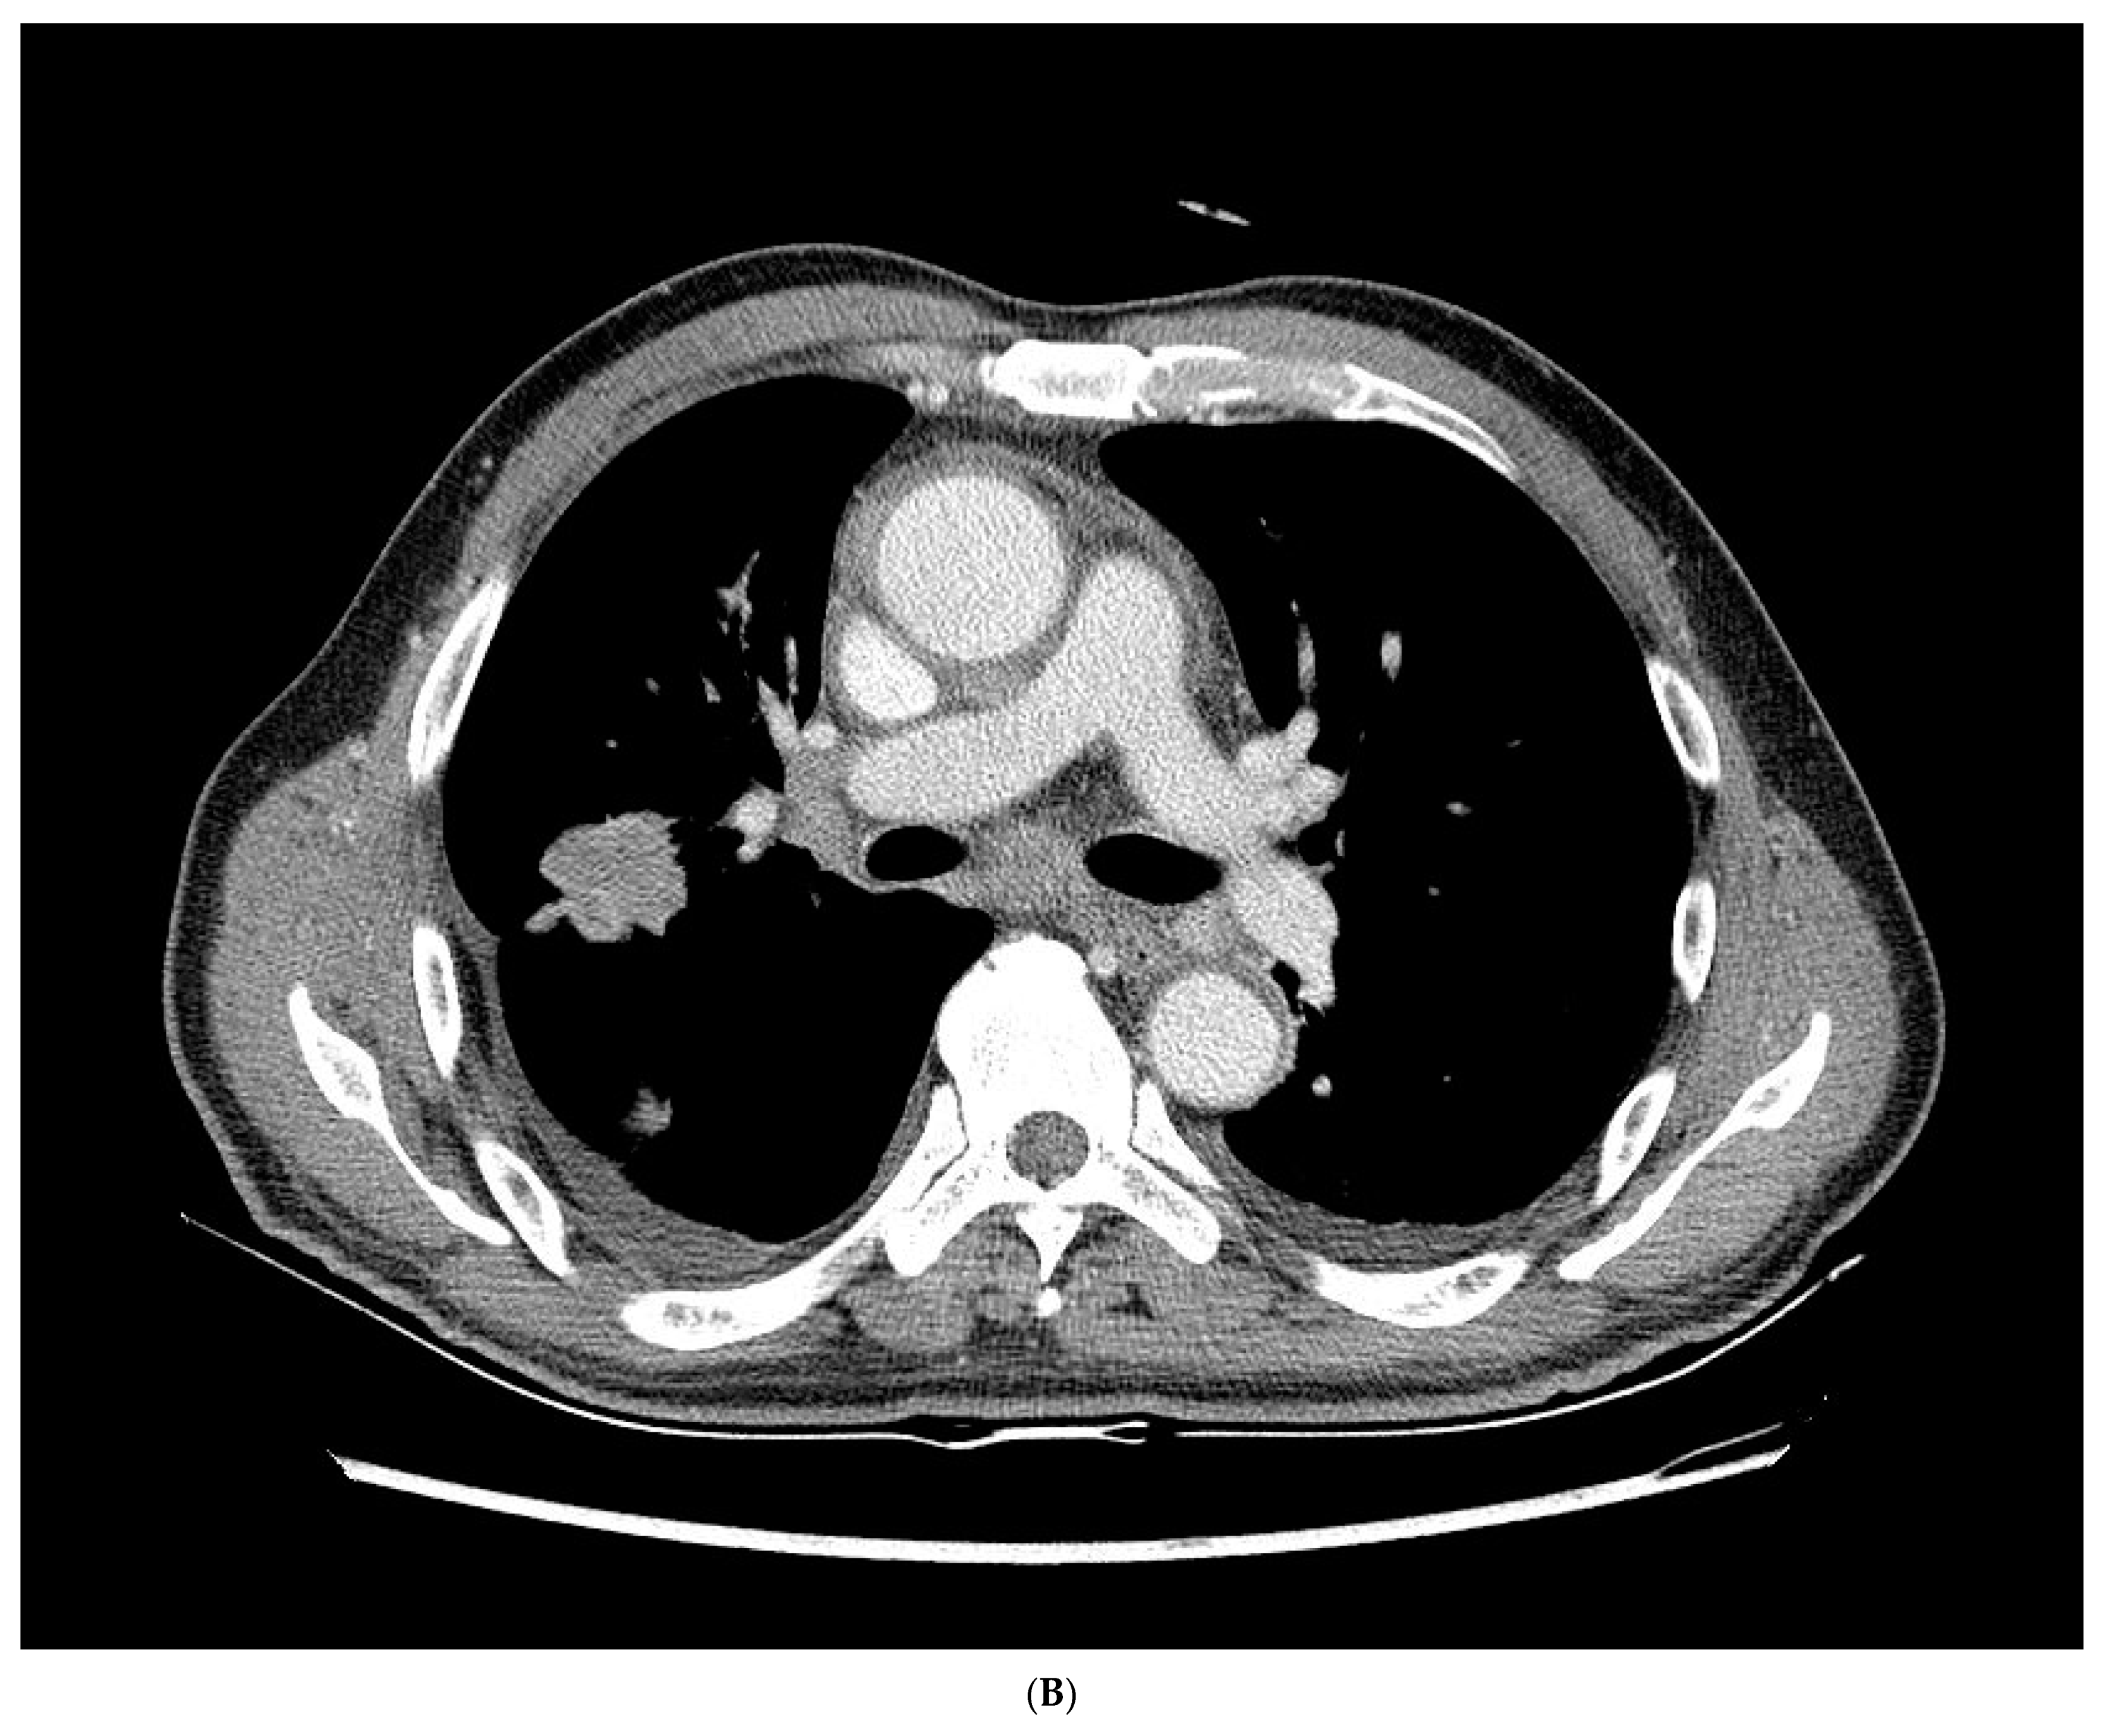

The chest radiography showed a massive right-sided pleural effusion (Figure 1A). Percutaneous catheter drainage was performed for the right-sided pleural effusion. The chest computed tomography showed a 3.3 cm × 3.0 cm mass in the right upper lobe (Figure 1B). The positron emission tomography/computed tomography revealed metastases in the left-sided supraclavicular lymph nodes, multiple bilateral mediastinal lymph nodes, and left scapula (Figure 2). The magnetic resonance imaging of the brain revealed multiple tiny cerebral and right cerebellar metastases (Figure 3). A percutaneous needle biopsy confirmed the diagnosis of lung adenocarcinoma (pT2aN3M1c, stage IVB); the analysis of the right-sided pleural effusion revealed metastatic adenocarcinoma. The genetic analysis revealed an exon 19 deletion in the EGFR gene. The laboratory tests, including the blood cell counts and chemistry, were within the normal ranges prior to treatment initiation. The patient was administered the EGFR-TKI afatinib (40 mg/day) as a first-line chemotherapy.

Figure 2.

(A–E) Positron emission tomography/computed tomography revealed metastases to multiple lymph nodes, includingleft supraclavicular lymph node, bilateral mediastinal areas, and left scapula.